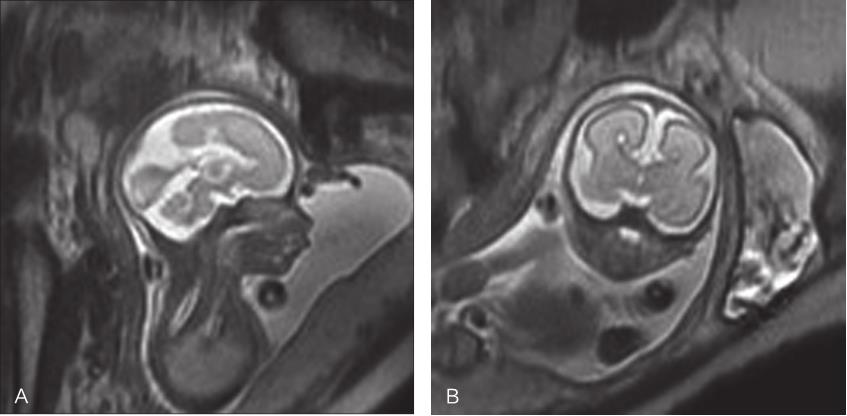

图2-3-1 孕22周胎儿头颅MRI平扫

A.矢状位T 2 WI,胎儿胼胝体未见显示;B.冠状位T 2 WI示双侧侧脑室分离呈“公牛角”样改变